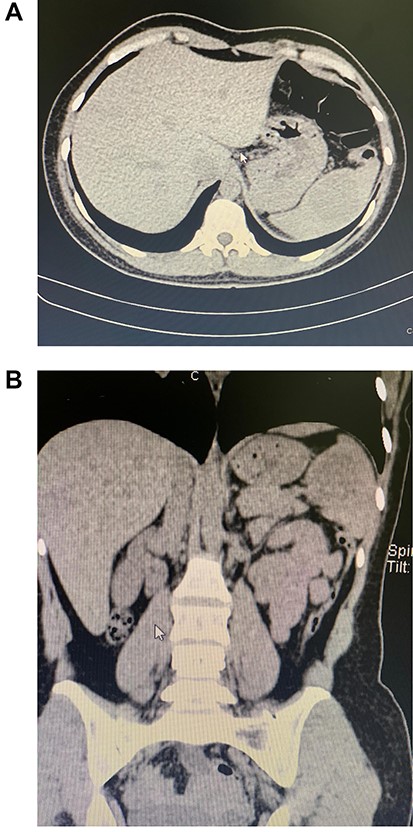

Patient is a 30-year-old female without past medical history. She had a 1-year history of mild abdominal pain in her upper left abdomen; at first, the pain was mild; nonetheless, the pain became much more severe throughout the year and was accompanied by nausea. Thus, she presented to the emergency room. On clinical examination, abdominal pain and tenderness along with a solid mass with severe pain on touch were discovered in her upper abdomen. No fever, vomiting, blood in the stool, or other symptoms were found. Due to this, a computed tomography (CT) revealed an enlarged spleen. It measured 15 × 10 × 5.5 cm, and within the spleen, a 5.4 × 5.1 cm mass and another 5.3 × 2.3 cm mass is seen (Fig. 1A and B). Laboratory exams revealed leukocytosis with neutrophilia and an elevated C-reactive protein.

(A) CT, a mass is seen in the spleen. (B) CT, the enlarged spleen with the mass in the upper pole.